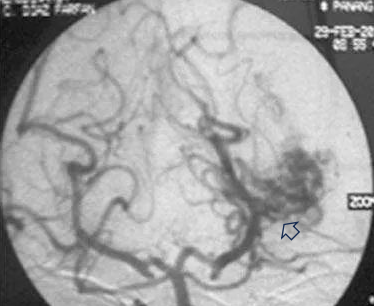

首次手术仅仅三个月后,大卫在学校突然昏迷,紧急送往医院后,检查为左侧颞角的脑动静脉畸形导致脑室内出血(图a、b)。

图(b)左侧 VA 造影,前后位像